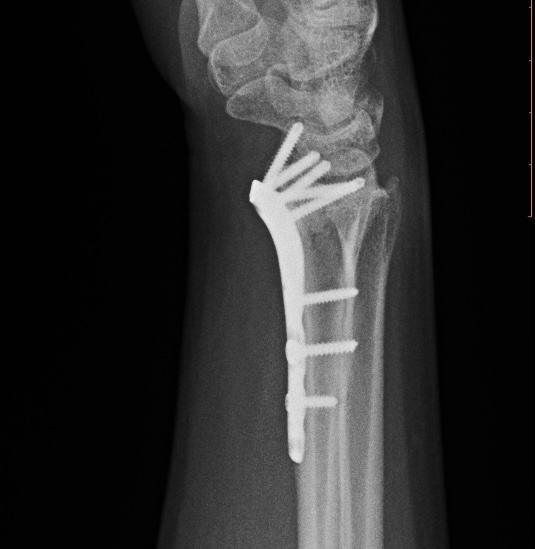

Клинический случай: внутрисуставной перелом дистального метаэпифиза лучевой кости — после операции

Контрольный осмотр и ранний послеоперационный результат.